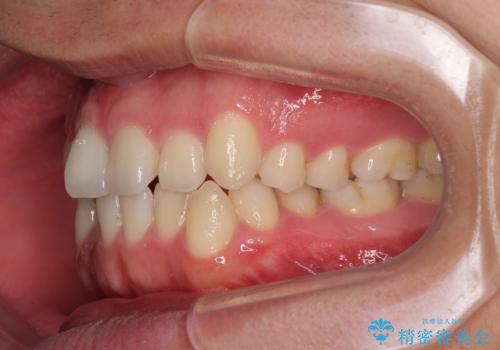

狭い歯列と前歯のデコボコ インビザラインによる矯正治療

- 上下前歯のデコボコを気にして来院された患者様です。

インビザラインによる上下歯列の拡大と、IPR(歯と歯の間を削る)にるスペースの獲得により、前歯のデコボコと狭い歯列を改善することとしました。

比較的軽度な歯列不正であったため、治療期間はそれほど長くはならないと予想されました。

しかしながら、あまりしっかりとマウスピースを装着していなかったため、思いの外期間が長引いてしまいました。

また、仕上がりの歯列にも若干の叢生が残ってしまいました。